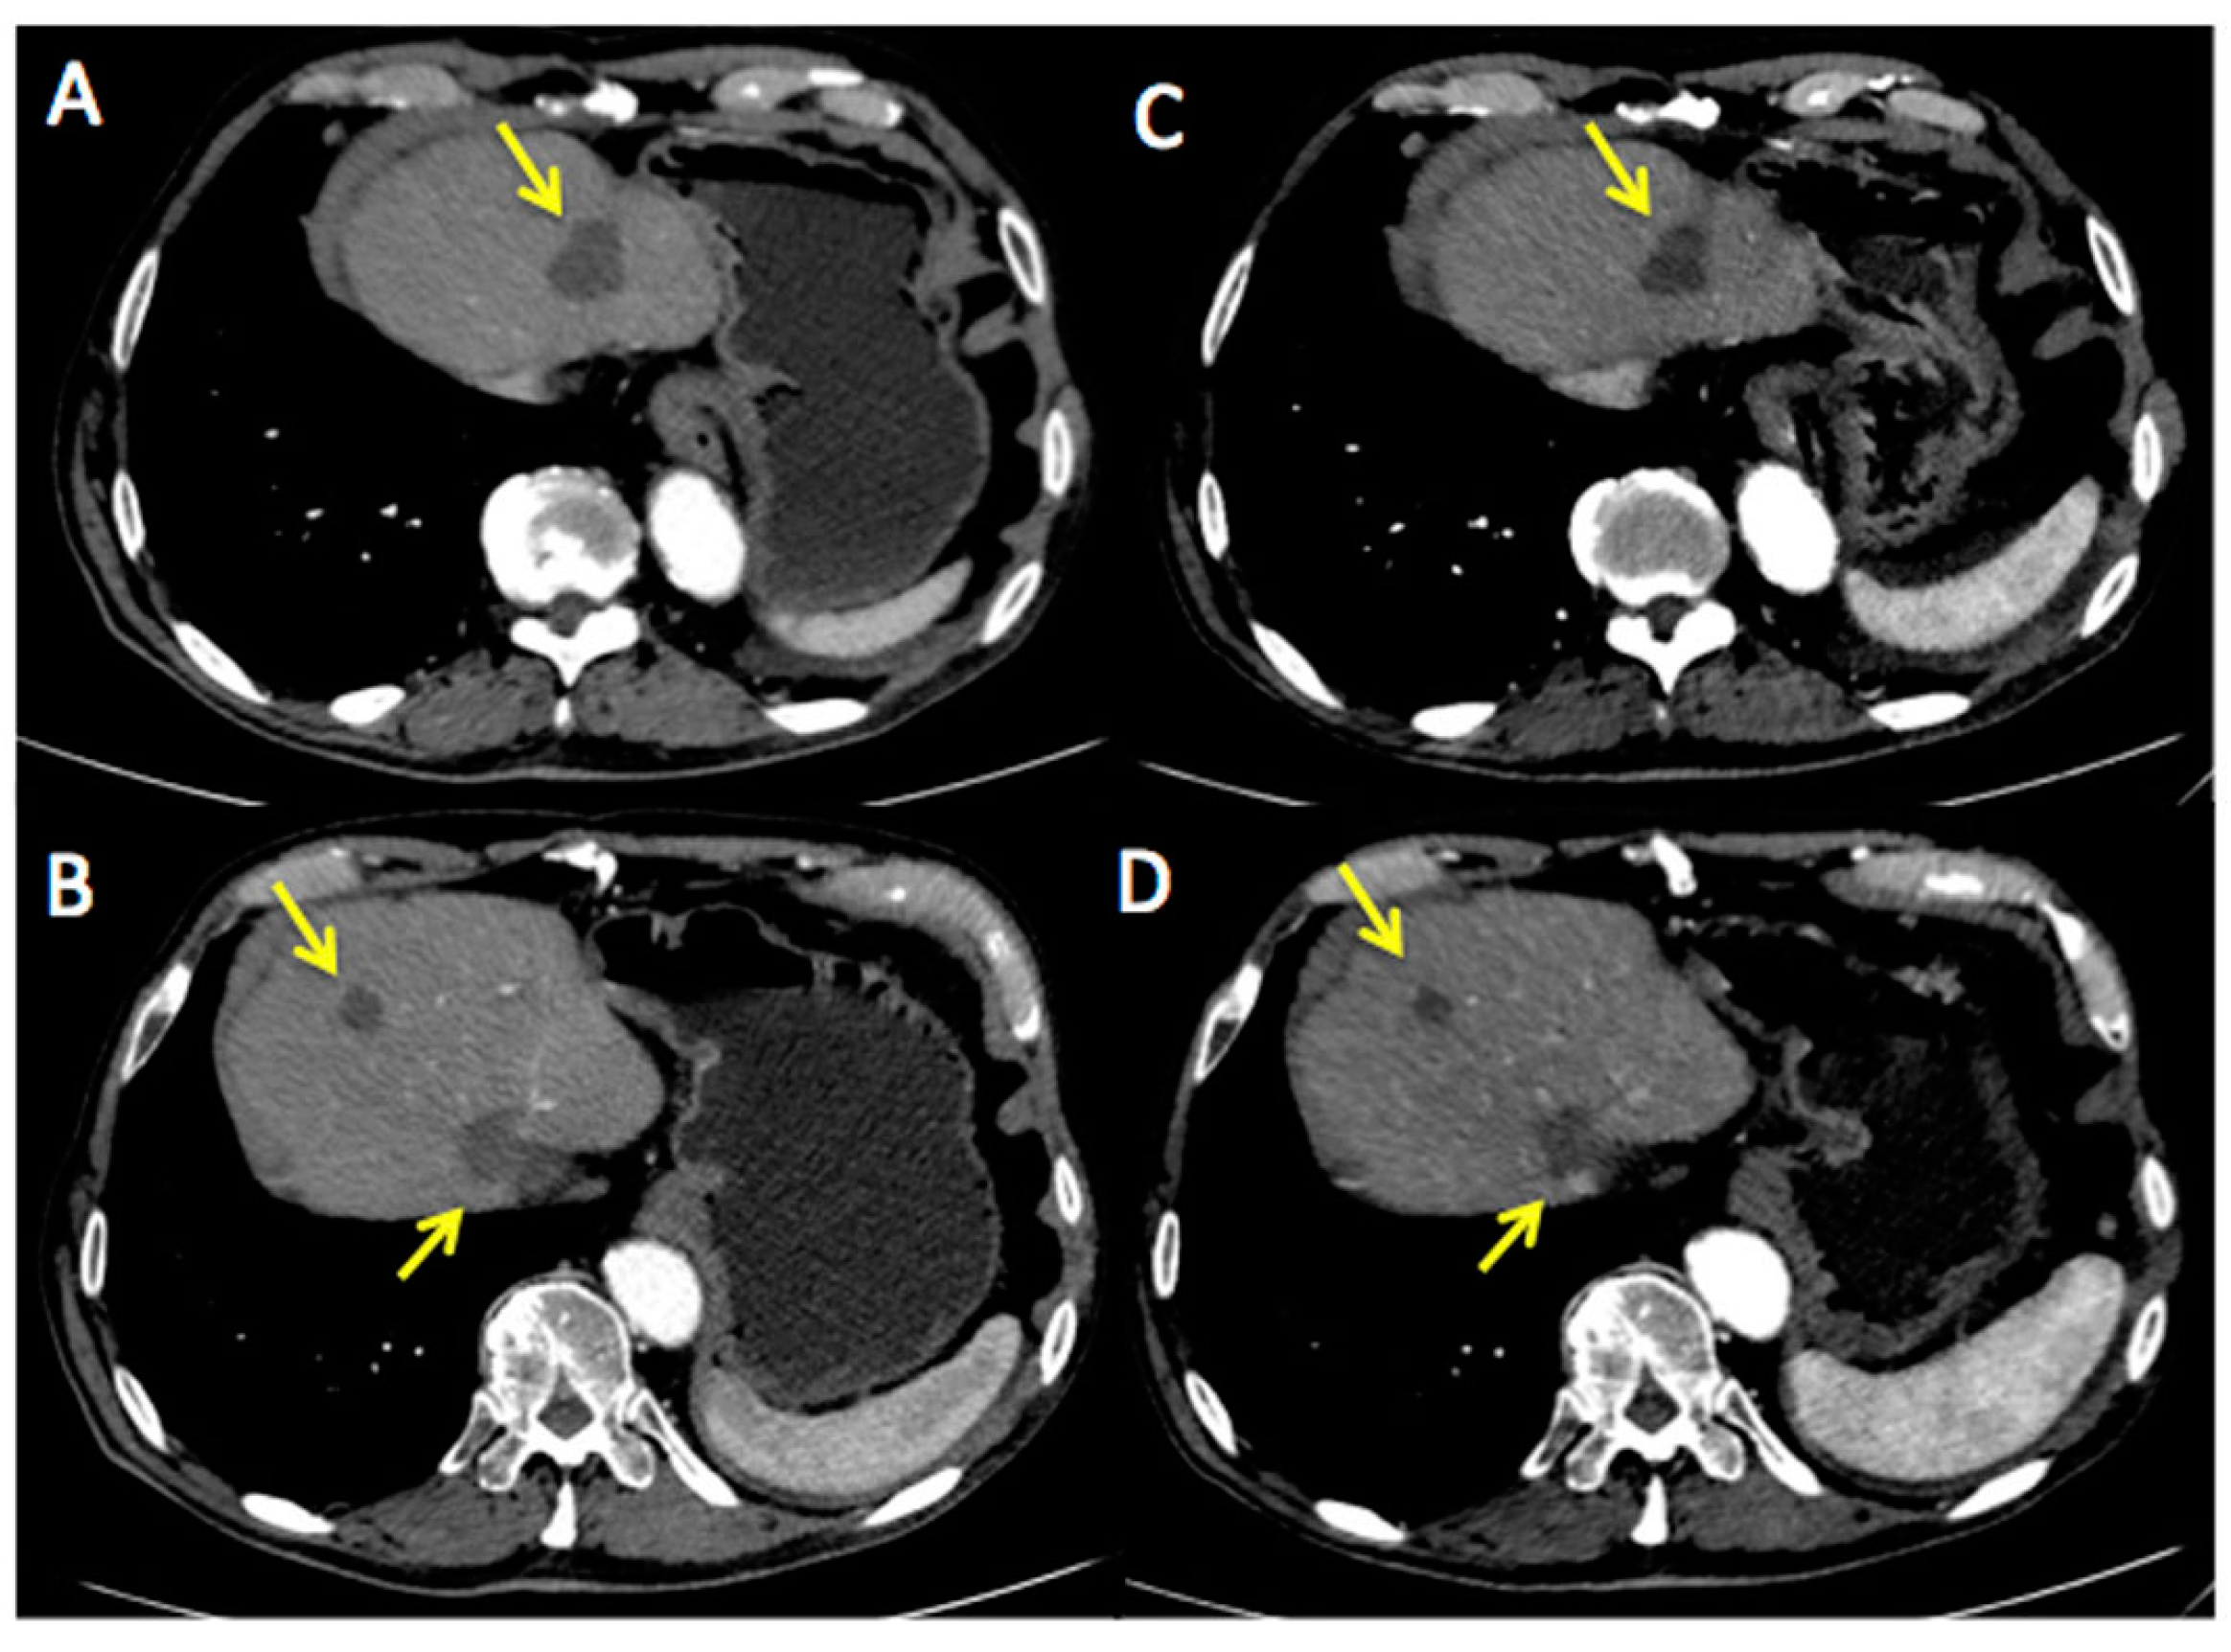

Figure 3 and Figure 4 represent two exemplar cases of patients judged to be PR and CR, respectively, at timepoint-2 evaluation.

Figure 4. A56-year-old female affected by ovarian cancer with liver and spleen metastasis, already treated with 12 cycles of Bevacizumab-based chemotherapy and 24 hyperthermia sessions on the abdomen, as first-line. Baseline MDCT (C) showed metastasis in III and IV segment of the liver (maximum diameter: 77 mm, green squares) and in the upper spleen (maximum diameter: 61 mm, green square). Baseline whole body 18F-FDG PET/CT (A) confirmed liver and spleen involvement by the increased 18F-FDG uptake (yellow arrows) detectable also on axial fused PET/CT images (B) in the same sites (green and red squares). Timepoint-2 MDCT (D) evaluation demonstrated significant size decrease of liver and spleen metastasis (yellow squares) with no evidence of 18F-FDG uptake on whole body PET/CT (E). According to mRECIST, patient was classified as CR. Ca125 value evaluated at baseline was 790 UI/mL; while Ca125 value evaluated at timepoint-2 was 12 UI/mL. Side effects reported were limited to asthenia and high blood pressure.